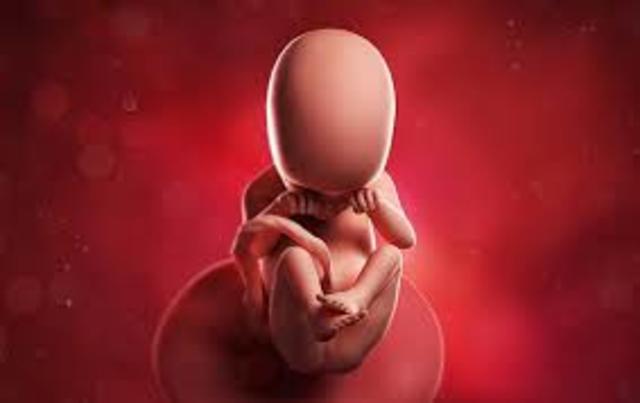

• Décimo séptima semana.

Décimo séptima semana.

El bebé mide entre 11 y 13 cm y pesa 100 gr, su aspecto se va parecido cada vez más a un recién nacido.

La grasa empieza a aparecer e todo su cuerpo llamado tejido adiposo y es importante para mantener el calor corporal y regular el metabolismo del organismo, el agua forma parte de la tercera pare del cuerpo del feto, la posición habitual es semiflexionada con las manos a la altura de la barbilla y los pies cruzados por debajo de la salida del cordón umbilical.